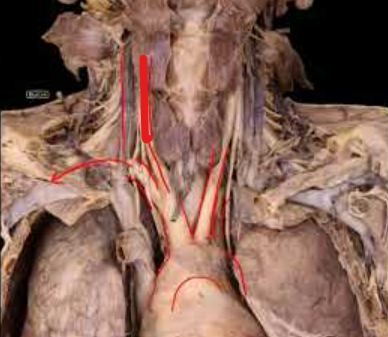

A

Brachiocephalic Trunk

Left Common Carotid

Right Common Carotid